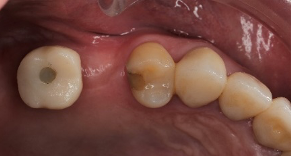

- 手術過程,在植入植體前先用導板定位,確認植牙位置及角度。

- 植牙當下不用劃開傷口無須縫合,鎖上癒合帽即可,也不需縫合傷口

待3.4個月後裝上全陶瓷牙冠完成植牙療程。整個療程過程輕鬆。